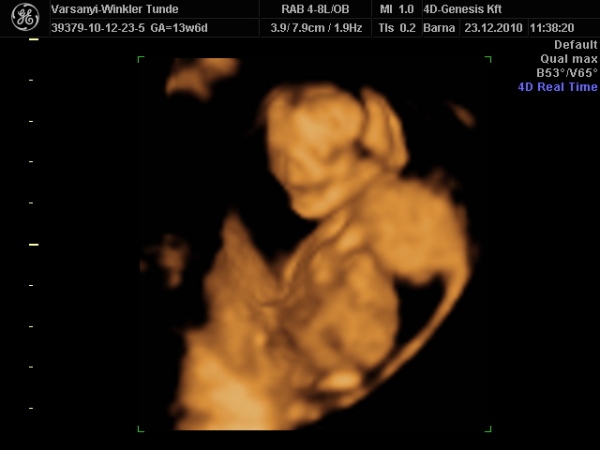

)2010.12.23 11:37